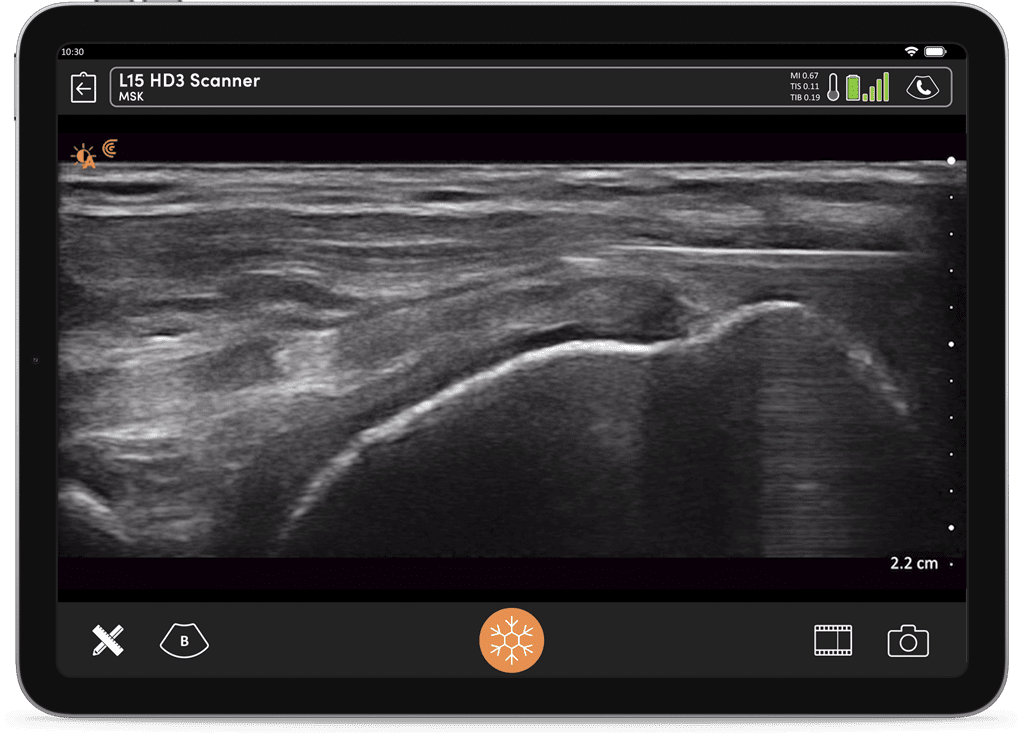

Images captured on same day with same patient

The portability and image quality of the L15 HD made it an easy decision. One of the other factors for my purchase was the excellent cloud-based database, workflow and reporting functions with Clarius.

The image quality is fantastic. The linear scanner is on par with compact systems, no question.

“The new AI from Clarius is a ground-breaking technology that will help with the education of new users to identify MSK structures. With the AI standardization of measurements, interobserver reliability problems will now be non-existent.“

What I was most blown away by was actually the new color Doppler feature. In addition to the actual quality of the image, you’re getting it wirelessly. It’s on par with any corded device I have.

Powered by artificial intelligence, 192 piezoelectric elements, and (not one but) eight beamformers, only Clarius HD3 delivers the high performance and image quality of compact-based systems in a small form factor that feels like a traditional transducer. You can confidently guide your needle to the target anatomy accurately every time.